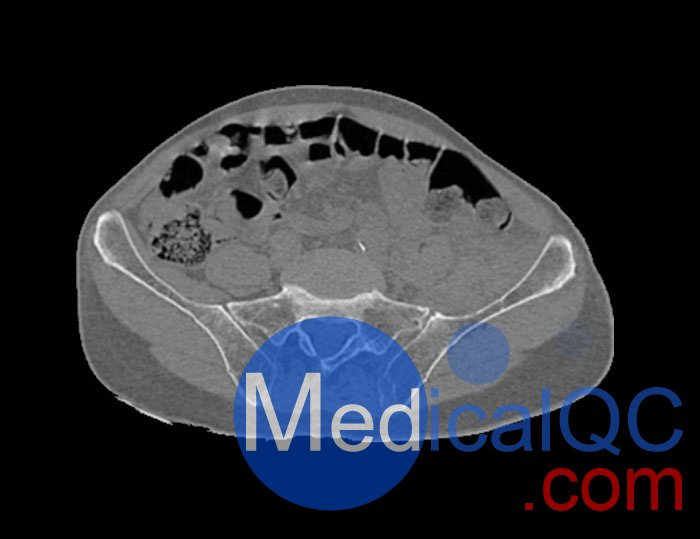

WEK54-01股骨頸骨折骨盆模型,WEK54-01骨盆模體模擬沒有靜脈造影劑的骨盆(天然)。它覆蓋了整個骨盆,直到第五腰椎。

左側(cè)股骨頸移位骨折。

該模型可用于 CT(包括 CBCT)和射線照相,以評估和優(yōu)化成像性能和后處理應(yīng)用,包括支持 AI 的應(yīng)用。它也適用于培訓(xùn)目的。

骨骼和軟組織的逼真模擬。